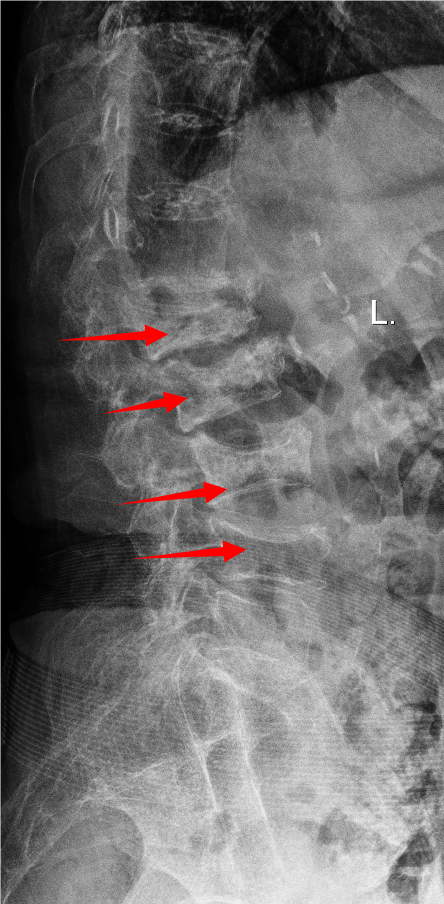

胸腰椎MRI检查结果显示:腰1椎体新近压缩性骨折伴积气,继发椎管狭窄;腰2、3椎体及腰4椎体上缘新近骨折。

影像学结果明确了患者为“骨质疏松伴多节段病理性骨折”,并伴有明显的脊柱后凸畸形和腰椎不稳。骨密度检测T值-4.25,提示重度骨质疏松。

影像学检查提示多节段脊柱病变

接诊后,科室为吴婆婆安排了详细的影像学检查,结果令人震惊。磁共振显示,她的骨折远非此前所知的一处,骨折下方的三节椎体腰2至腰4多个椎体都出现了新鲜压缩性骨折。更关键的是,最初的腰1椎体骨折并未愈合,属于“骨折不愈合”状态,并在重力作用下逐渐塌陷,导致脊柱后凸畸形(俗称“驼背”)。

术前(左)和术后(右)对比: 术后脊柱后凸矫正,骨折椎体强化固定